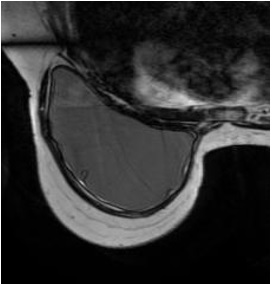

Figure 1. STIR with water SAT: Fat = dark, Water = dark, Silicone = bright

Figure 2. STIR: Fat = dark, Water = vrey bright, Silicone = bright

Figure 3. T2 no SAT: Fat = bright, Water = bright, Silicone = bright

Figure 4. FSE fat SAT: Fat = medium, Water = bright, silicone = dark

Figure 5. STIR with silicon suppressed: Fat = dark, Water = bright, Silicone = dark